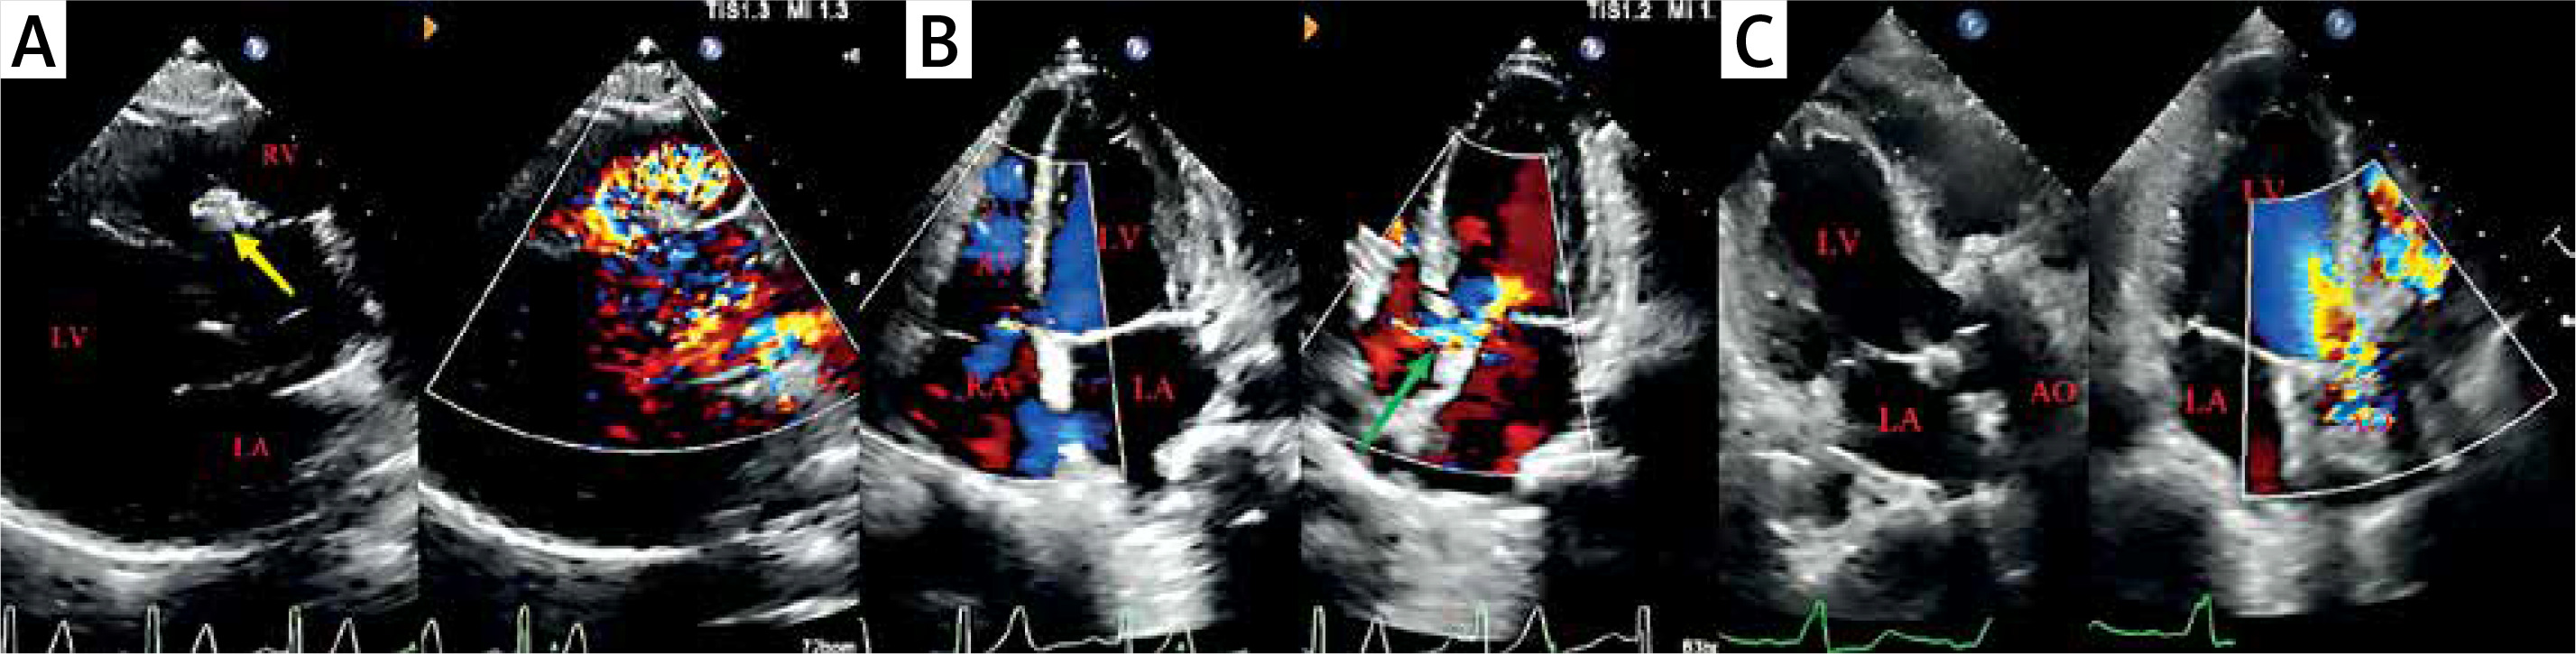

Figure 2

Echocardiographic images of the patient before and after the second surgery. A, B – Echocardiographic images before the second surgery; the yellow arrow is the occluder; the green arrow is the ventricular septal defect. C – Echocardiographic images after surgical operation

LA – left atrium, LV – left ventricle, RA – right atrium, RV – right ventricle, AO – ascending aorta.

On follow-up after half a year, he was readmitted for shortness of breath and chest tightness. At the apex and the left sternal border a pathological holosystolic murmur was heard. Re-examination of the laboratory results showed elevated total antibodies to syphilis and positive serotonin with a titer of 1 : 1. Echocardiography (Figures 2 A, B) showed whole heart enlargement and right ventricular wall thickening. The right SoV aneurysm expansion area was 30 × 24 mm with partial calcification of the aneurysm wall, on which hyperechogenicity of the occluder can be seen and protrusion into the right ventricular outflow tract, and a shunt signal of about 3.2 mm in width can be seen on the left side of the blocker, with a peak flow velocity of 3.88 m/s, and a peak pressure difference of 60 mm Hg. The perimembranous ventricular septum appears to be continuously interrupted with a width of about 4 mm, with a velocity of 4.97 m/s, and a peak pressure difference of 99 mm Hg. Aside from this, there was pulmonary artery dilatation, moderate-to-severe aortic regurgitation, and normal left ventricular systolic function. Surgical treatment should be provided to prevent the development of potentially life-threatening complications. Intraoperatively, a 2.5 × 2.5 cm septal defect was seen immediately below the right coronary annulus. Subsequently, aortic valve replacement, occluder removal, repair of ruptured aortic sinus aneurysm, repair of ventricular septal defect, aortic root angioplasty, and implantation of a temporary pacemaker were performed. Postoperative echocardiography (Figure 2 C) showed successful repair of the VSD and right coronary sinus aneurysm rupture, significant reduction of aortic regurgitation, and normalization of pulmonary artery pressure. Pathology of the aortic valve suggested fibrous tissue hyperplasia with collagenization and calcification, focal mucinous degeneration, and a small amount of lymphocytic infiltration. Post-operatively, the patient was medicated with furosemide, sildenafil, macitentan tablets, and warfarin, recovering well, and was finally discharged 16 days after surgery. In addition, patients are released from the hospital to receive penicillin treatment in dermatology outpatient clinics.